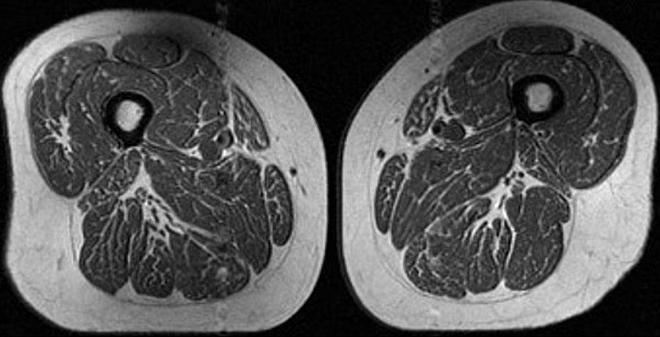

L’immagine più impressionante è quella dei muscoli della coscia di una donna di 62 anni che ha dichiarato di ricavare l’87% delle calorie da cibi ultraprocessati. Le sue cosce sembrano una bistecca di Wagyu, la costosissima carne giapponese nota per la distribuzione del grasso all’interno del muscolo in sottili striature bianche che ricordano il disegno di una superficie marmorea. Nel suo caso, le calorie provenivano soprattutto da prodotti da forno industriali, cioccolato, barrette e bevande zuccherate. Un’immagine simile è emersa anche dalla risonanza di una donna di 61 anni, il cui apporto calorico derivava però “solo” per il 29% da cibi ultraprocessati.

risonanza magnetica coscia 62 enneRisonanza magnetica della coscia di una partecipante di 62 anni allo studio la cui dieta è composta per 87% da cibi ultraprocessati

Il dato più interessante è che la donna che assumeva “solo” il 29% delle calorie da cibo ultraprocessato aveva un indice di massa corporea più alto e praticava meno attività fisica rispetto alla donna che arrivava all’87%; eppure quest’ultima mostrava una quantità di grasso marezzato nei muscoli nettamente superiore.